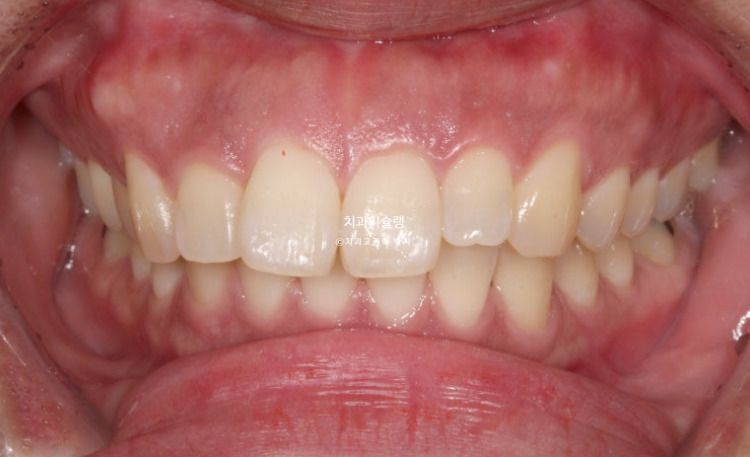

Finally, three years after treatment began, the appliances were removed and treatment was completed.

The midline and deep overbite have improved.

A stable, secure occlusal relationship is a given.

Let’s compare the before and after.